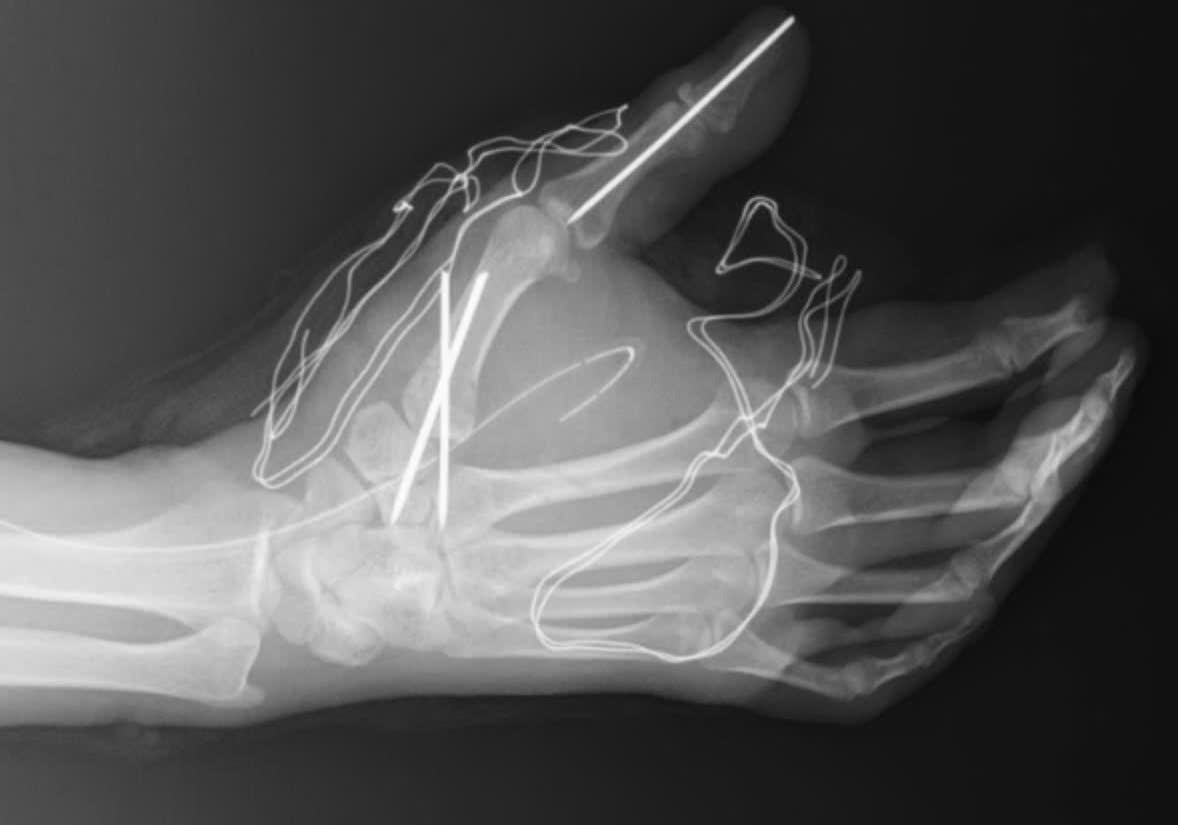

Sự việc xảy ra vào chiều ngày 27/1 tại Hà Nội, khi người thanh niên này đốt pháo tự chế Lao Động. Hậu quả là bàn tay của nạn nhân bị dập nát nghiêm trọng, cần phải nhập viện để điều trị.

Vụ nổ pháo đã gây ra những tổn thương nặng nề về thể chất cho nạn nhân Lao Động. Anh phải đối mặt với nguy cơ mất đi một phần hoặc toàn bộ chức năng của bàn tay.

Hiện tại, nạn nhân đang được điều trị tích cực tại bệnh viện Lao Động. Các bác sĩ đang nỗ lực để cứu chữa và phục hồi chức năng cho bàn tay của anh. Chính quyền địa phương chưa có thông tin về vụ việc.